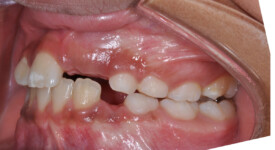

This is an example of a teenage patient with photographs of their smile before and after treatment at Braceline. Our orthodontic treatments are designed to provide maximum results in minimal time and to help you achieve the smile you always wanted!

Before Transformation!